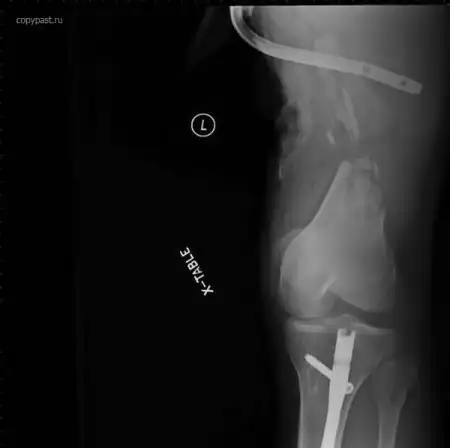

У человека в бедре были металлические стержни, которые ему поставили после аварии

на мотоцикле.

После еще одной аварии от очень сильного удара стержень разорвало.